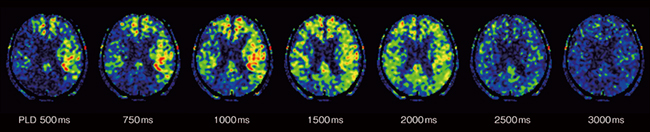

Multiphase ASLは,血流信号を飽和させた画像と血流信号を飽和させていない画像を差分することで,PLD(post labeling delay)によらず,従来のASL-perfusionよりも背景信号を抑制した画像を得ることができる撮像技術です。この技術を利用することにより,複数の異なるPLDの灌流画像を取得でき,血液到達の遅れをより正確に視覚化することができるようになりました(図8)。また,vascular crusherの役割を果たす「MSDE機能」と併用することで,血管内に残存するラベルされた血液の信号を抑制することも可能です。

ECHELON Synergyで撮像した灌流画像を「SYNAPSE VINCENT Core」*6で解析することが可能です。ECHELON Synergyで取得した複数PLDの画像からATT map(arterial transit time:ラベリングされた血液の到達時間)とATTを考慮したCBF map(cerebral blood flow:脳組織の血流)を作成し,血流動態をカラー表示および数値化することで評価を容易にするmapを作成することができます(図9)。

図8 Multiphase ASL

複数の異なるPLDの灌流画像により,血液到達の遅れをより正確に視覚化することが可能。